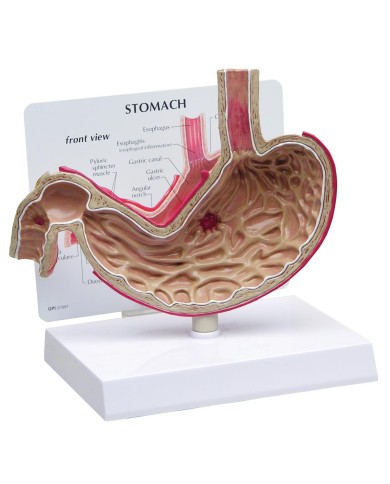

I Modelli anatomici 3B scientific ed Erler Zimmer sono quanto di meglio esista per studiare l'anatomia del corpo umano, il catalogo dei modelli anatomici comprende modelli di cranio, scomponibili, colorati, crani anatomici, crani su cavalletto, e il modello di punta, il cranio in 22 parti, ad incastro magnetico.

I modelli anatomici didattici sono riproduzioni di strutture anatomiche perfettamente uguali a quelle vere, i modelli di ossa sono realizzati dalla scansione di ossa vere, l'esperienza tattile è assolutamente realistica, ed anche il peso delle ossa corrisponde all'incirca al peso delle ossa vere.

Sono indispensabili per lo studio dell'anatomia umana, oggi è possibile osservare le strutture anatomiche senza la necessità di dissezionare cadaveri o di effettuare studi pericolosi su pazienti vivi.

Gli studenti di medicina utilizzano i modelli anatomici per i loro studi di anatomia umana, studiare l'anatomia sui libri non basta, un modellino anatomico permette uno studio molto più accurato che una foto o un disegno su un libro.

Medici, fisioterapisti, osteopati e professionisti sanitari utilizzano i modelli anatomici per dare spiegazioni ai pazienti sulle patologie, risparmiando tanto tempo prezioso durante la spiegazione, che diventa molto più efficace.